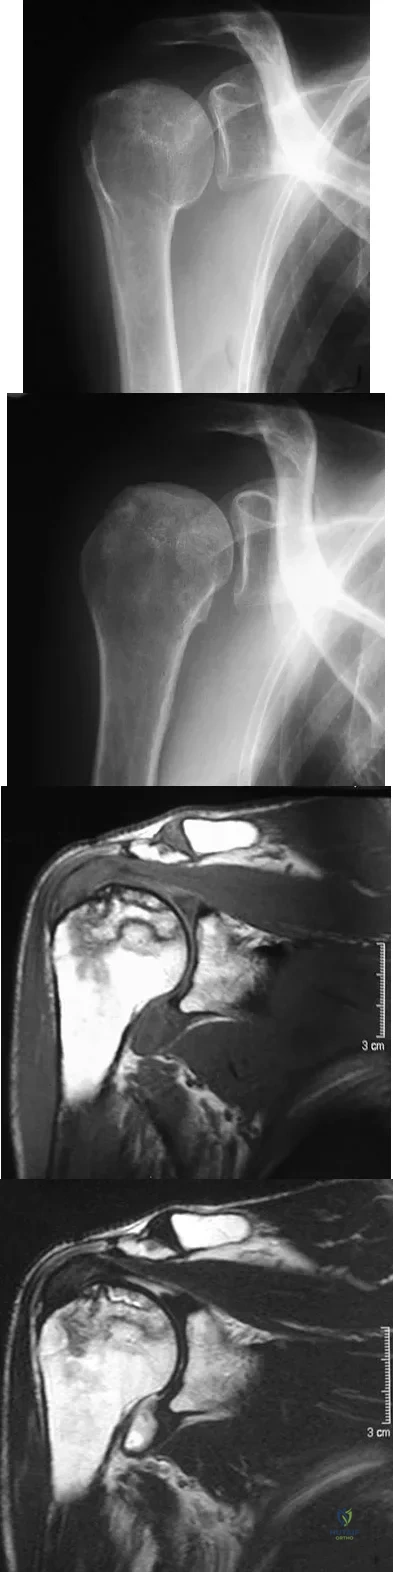

A 58-year-old woman with a history of severe asthma and long-term prednisone use reports a progression of chronic shoulder pain for the past 6 months. Radiographs and MRI scans are shown in Figures 30a through 30d. What is the most likely diagnosis?

Explanation